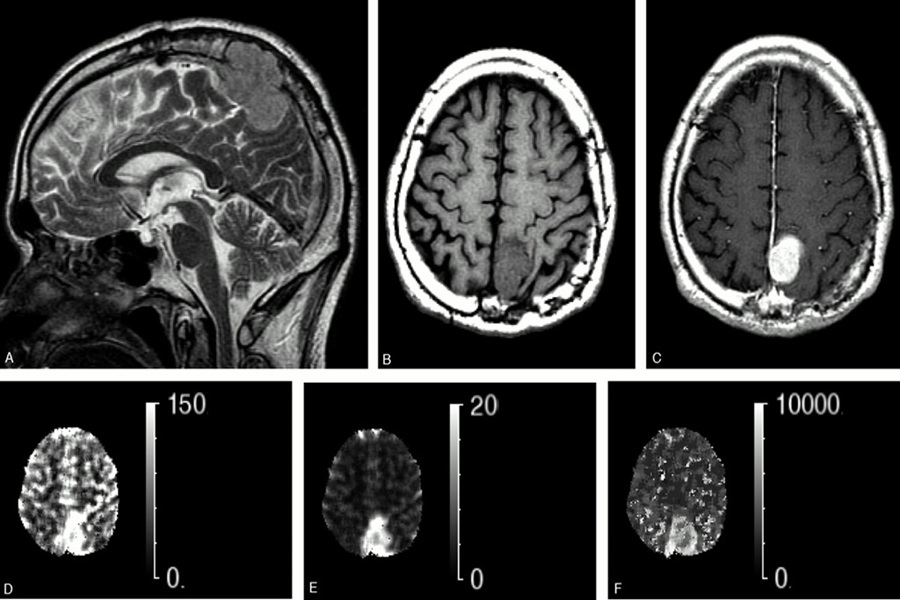

اهمیت این نوع تومور به حدی است که تشخیص آن باید بلافاصله توسط تیم درمانی متخصص بررسی شود. علائم ممکن است شامل سردردهای مکرر، مشکلات بینایی (به ویژه کاهش دید محیطی) و تغییرات هورمونی باشند. دکتر القاسی با تخصص ویژه در جراحی تومورهای هیپوفیز از طریق رویکردهای پیشرفته و آندوسکوپیک مغز، که روشهای کم تهاجمی هستند، این تومورها را با دقت بالایی خارج میکنند و در حفظ عملکرد غده و بینایی بیمار بسیار موفق هستند. ارزیابی اولیه شامل آزمایش خون برای بررسی سطوح هورمونها و تصویربرداری MRI است.

تومور هیپوفیز که بینایی را تحت تاثیر قرار میدهد، نمونهای کلاسیک از یک تومور خوشخیم است که به دلیل موقعیت استراتژیک خود، نیازمند جراحی فوری است. همانطور که پیشتر گفته شد، غده هیپوفیز درست در زیر مغز قرار دارد و درست بالای آن، محل تقاطع عصبهای بینایی (کیاسمای بینایی) قرار دارد. اگر تومور هیپوفیز رشد کرده و به این ساختار فشار وارد کند، اولین علامت کاهش دید محیطی یا تونل بینایی خواهد بود. این وضعیت میتواند به سرعت منجر به نابینایی دائمی شود.

در این شرایط، جراحی هدف اصلی خود را بر برداشتن فشار از روی عصبهای بینایی قرار میدهد. دکتر القاسی از جراحی آندوسکوپیک مغز، از طریق بینی و سینوس اسفنوئید، برای دسترسی به این تومورها استفاده میکنند. این روش کم تهاجمی است و امکان دید بهتر و بهبودی سریعتر را فراهم میآورد. جراحی تومور هیپوفیز، ترکیبی از تخصص جراحی مغز و اعصاب و غدد درونریز را میطلبد تا هم بینایی حفظ شود و هم عملکرد هورمونی بدن به حالت عادی بازگردد.